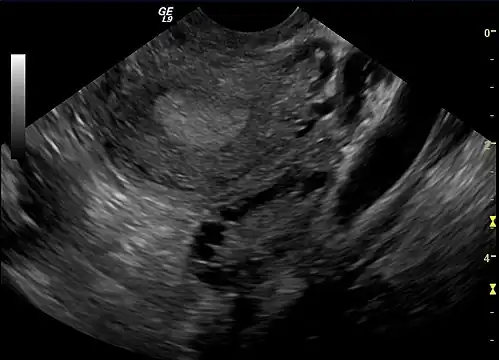

The syndrome acquired its most widely used name due to the common sign on ultrasound examination of multiple (poly) ovarian cysts. These "cysts" are immature ovarian follicles. The follicles have developed from primordial follicles, but this development has stopped ("arrested") at an early stage, due to the disturbed ovarian function. The follicles may be oriented along the ovarian periphery, appearing as a 'string of pearls' on ultrasound examination.[63]

Gynecologic ultrasonography first looks for small ovarian follicles.[75] To count as polycystic ovaries, at least 20 follicles need to be present, smaller than 9 mm. This used to be 12 in older diagnostic criteria.[16] A less clear marker of PCOS is enlarged ovaries.[75] Ovary need to be at least 10 cm3 to count.[16] For sexually active individuals or those that agree, a transvaginal ultrasound approach is preferred. Alternatively, AMH levels can be tested in the blood.[75] Laparoscopic examination may reveal a thickened, smooth, pearl-white outer surface of the ovary. This would usually be an incidental finding if laparoscopy were performed for some other reason, as it would not be routine to examine the ovaries in this way to confirm a diagnosis of PCOS.[78]